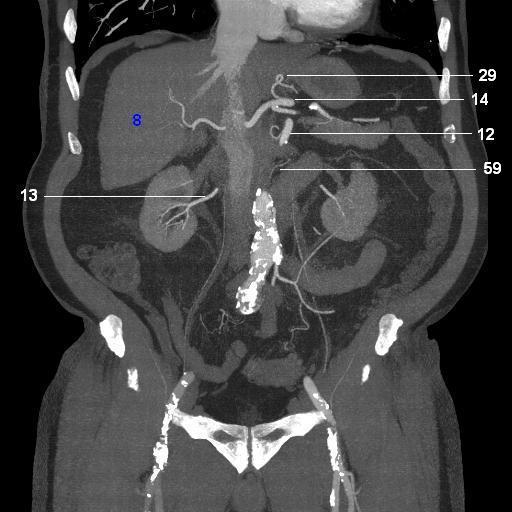

8.   liver

12. SMA

13. right renal artery

14. celiac artery

29. left gastric artery

59. posterior inferior pancreaticoduodenal a.